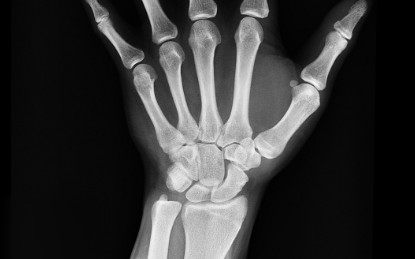

인간의 뼈는 수명주기 동안 끊임없이 재생된다. 골다공증은 이 과정이 제대로 이루어지지 않아 뼈의 분해 속도가 새로운 뼈가 생성되는 속도를 앞지르는 질환이다. 시간이 지날수록 뼈가 약해지고 쉽게 부러질 수 있다. 나이, 성별, 약물 복용, 식습관, 흡연과 음주, 유전 등 다양한 요인이 골다공증에 영향을 미치는 것으로 알려져 있으며, 골다공증은 서서히 진행된다. 건강검진을 통해 예방할 수 있지만, 많은 경우 사람들은 뼈가 부러지기 전까지 자신이 골다공증을 앓고 있는지조차 모른다.

국제학술지 ‘오스테오포로시스 인터내셔널(Osteoporosis International)’에 발표된 새로운 연구는 미세플라스틱 노출을 잠재적인 새로운 위험 요인으로 추가했다. 연구진은 미세 및 나노플라스틱이 뼈에 미치는 영향을 다룬 62편의 과학 논문을 검토했으며, 다양한 실험실 및 동물 실험을 분석했다. 그 결과 미세플라스틱이 파골세포 형성을 촉진한다는 사실을 발견했다. 파골세포는 골수의 줄기세포에서 만들어지며, 오래되거나 손상된 뼈를 제거하는 골흡수(resorption) 과정을 통해 뼈 조직을 분해한다.

연구는 또한 미세플라스틱 입자가 뼈와 관련한 세포 생존율을 낮추고, 세포의 조기 노화를 유도하며, 유전자 발현을 변화시키고, 염증 반응을 유발할 수 있다는 사실도 밝혀냈다. 이러한 복합적인 효과는 파골세포가 재생되는 양보다 더 많은 뼈 조직을 파괴하는 불균형을 초래하고, 결국 뼈 구조가 빠르게 약화된다.

동물 실험 분석에서 연구진은 미세플라스틱이 체내에 축적되면 백혈구 수치가 감소한다는 사실을 밝혀냈는데, 이는 골수 기능의 변화 가능성을 시사한다. 또 동물 연구들은 미세플라스틱이 파골세포에 미치는 영향이 뼈 미세 구조의 악화, 비정상적인 세포 구조 형성과 관련이 있으며, 이로 인해 뼈 취약성, 변형, 골절 위험이 증가할 수 있음을 시사했다.